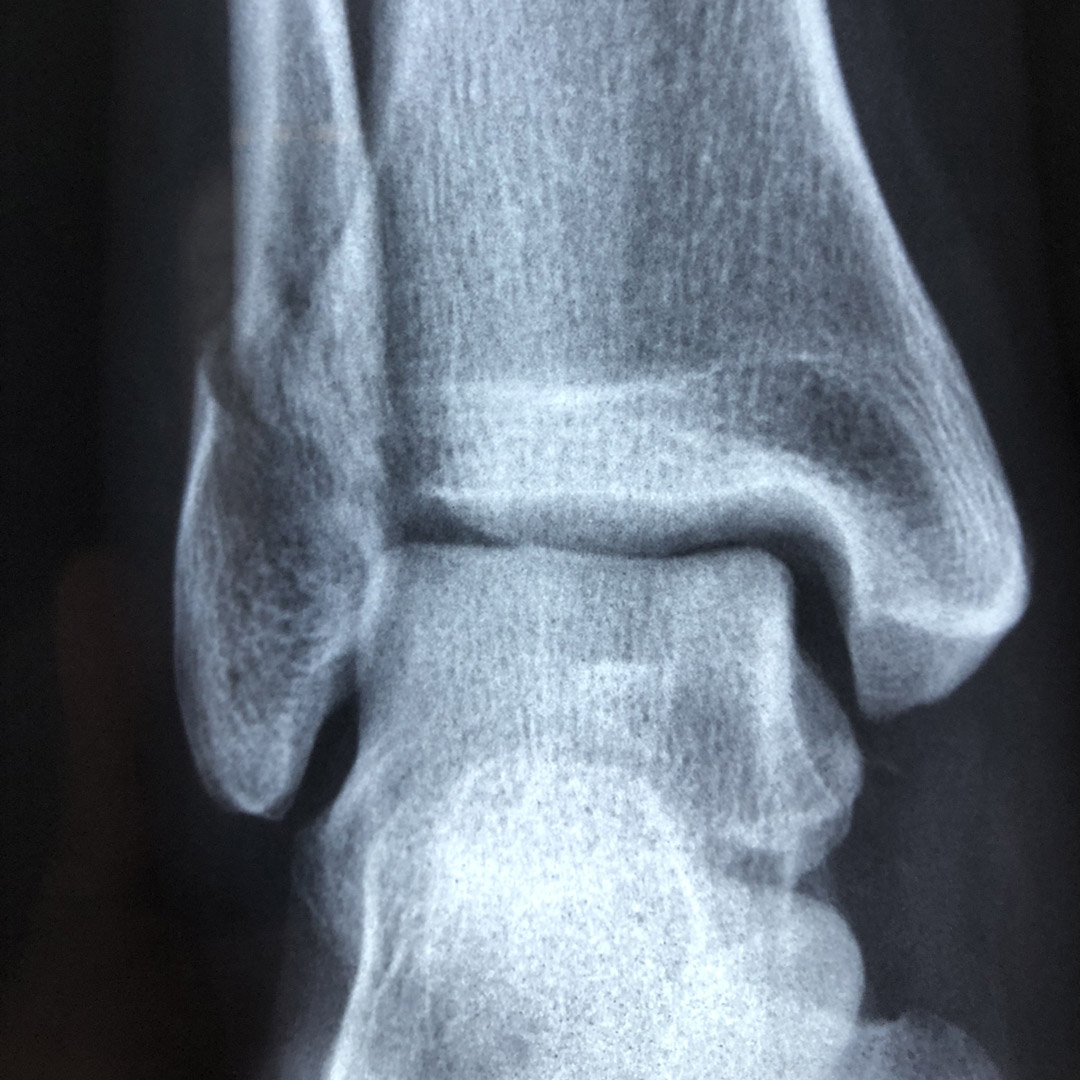

Radiographie numérique haute résolution